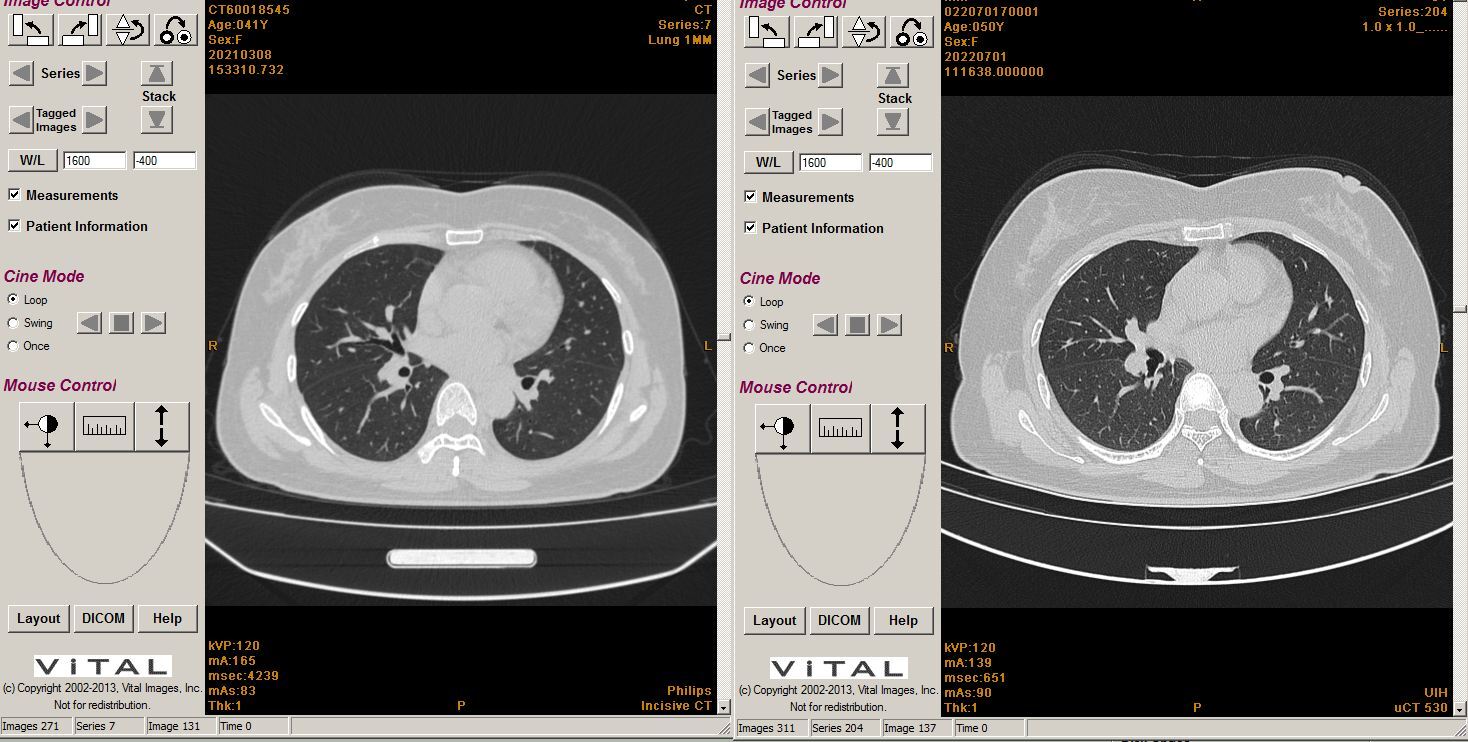

三甲

三甲

谭先华

副主任医师

武汉市第五医院

放射科

只言片语 之 (7)